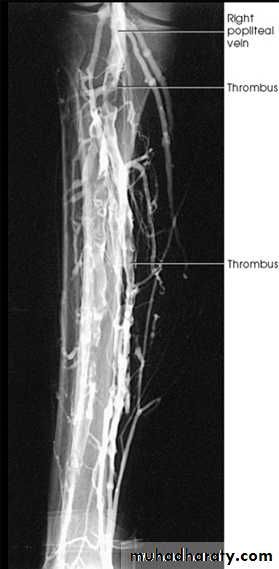

DVT